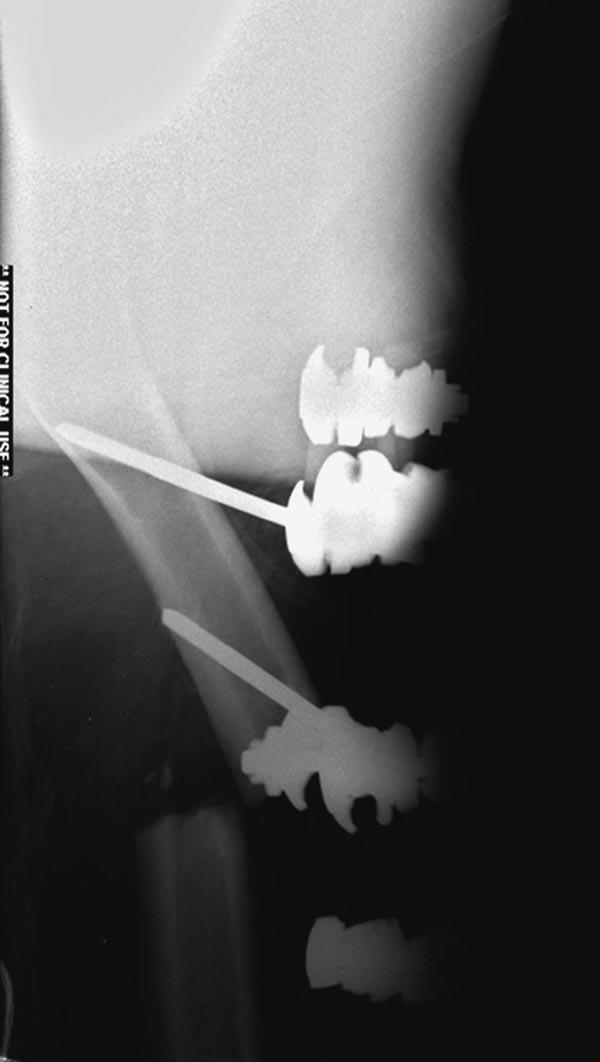

1.Вправление вывиха бедра, репозиция, остеосинтез перелома шейки бедра

2.Репозиция перелома таранной кости

3.После компенсации состояния внутренний остеосинтез диафиза и

дистального метафиза правого бедра.